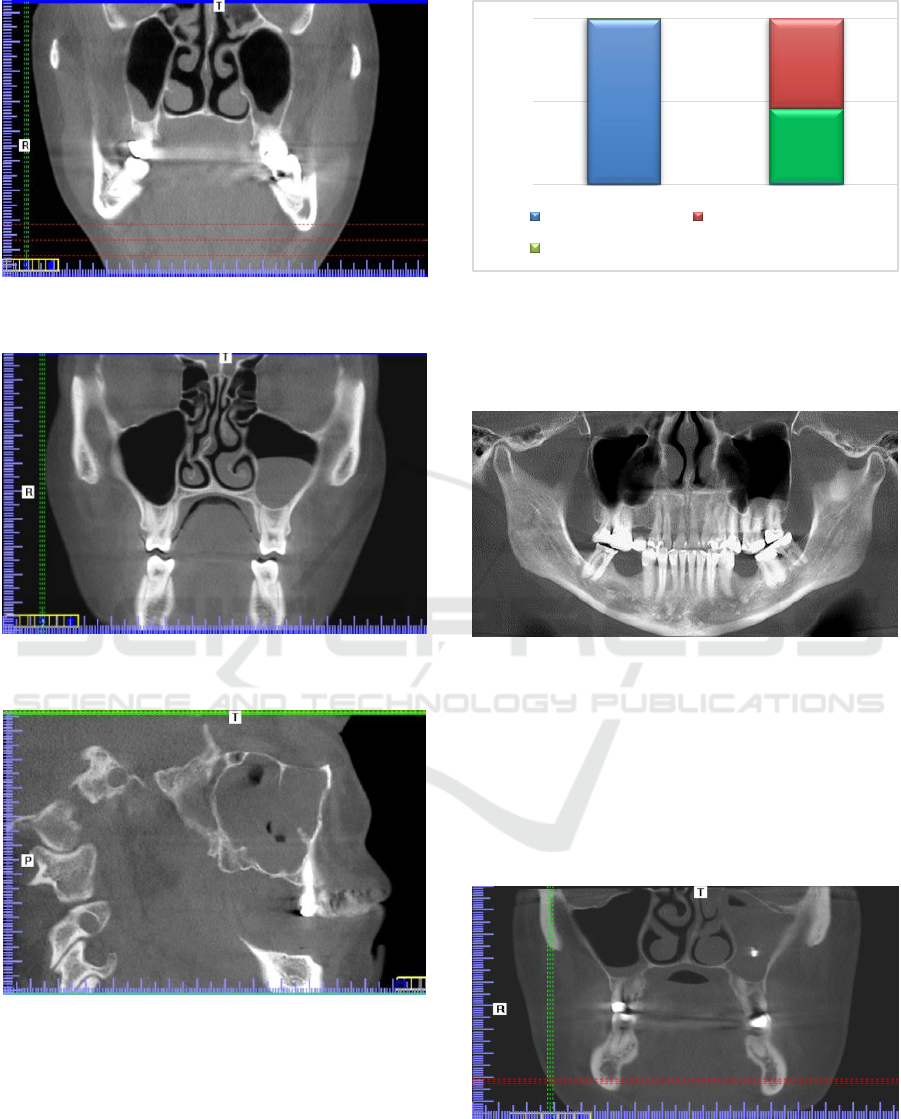

Volumetric Tomography is a valuable x-ray imaging

technique useful in the differential diagnosis of TM

dysfunction. The laying on of symptoms that mask

the main disease means that frequently, without addi-

tional examinations, it is not possible, in a univocal

way, to describe the type and extent of a disease. The

diagnosis of functional disorders of the muscular of

the chewing systems should take into account the dis-

ease lesions in the maxillary sinus. Detection of vari-

ous pathological processes occurring in the sinuses

paranasal, during of the diagnosis of dysfunction of

the chewing organ is not uncommon.

Limiting the imaging field in a volumetric tomog-

raphy study significantly reduces the diagnostic po-

tential of the study. The advantage of the possibility

of additional evaluation of the collateral sinuses and

the diagnosis of the underlying disease process is un-

doubtedly greater.